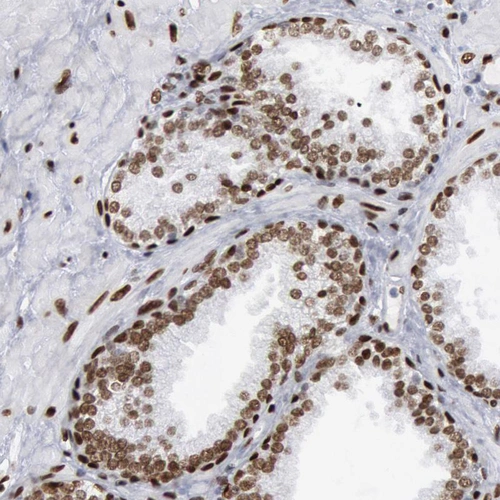

Immunohistochemical staining of human cerebellum, lymph node, prostate and testis using Anti-MECP2 antibody HPA001341 (A) shows similar protein distribution across tissues to independent antibody HPA000593 (B).